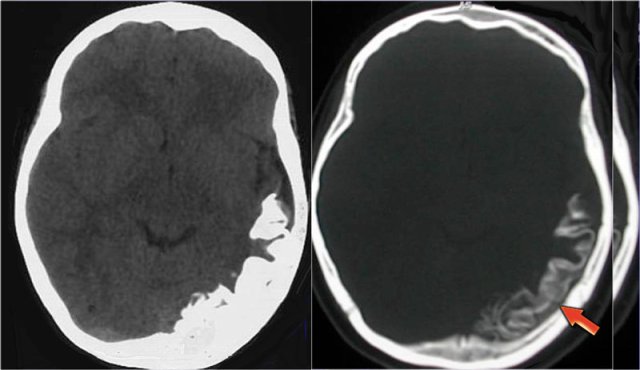

T2WI and T2* gradient echo show multiple cavernomas.

Notice the popcorn appearance with peripheral rim of hemosiderin on the T2WI.

The lesions are almost completely black on the gradient echo due to blooming artefacts.

T2* and susceptibility weighted imaging (SWI) markedly increase the sensitivity of MRI to detect small cavernomas.

The five black dots in the left cerebral hemisphere on the T2* are also cavernomas and are not visible on the T2WI.

The unenhanced CT shows a small calcification in the right lentiform nucleus.

Enhanced CT shows a venous anomaly draining the cavernoma into the right internal cerebral vein.

Coronal T2WI shows the venous anomaly as a curvilinear flow void.